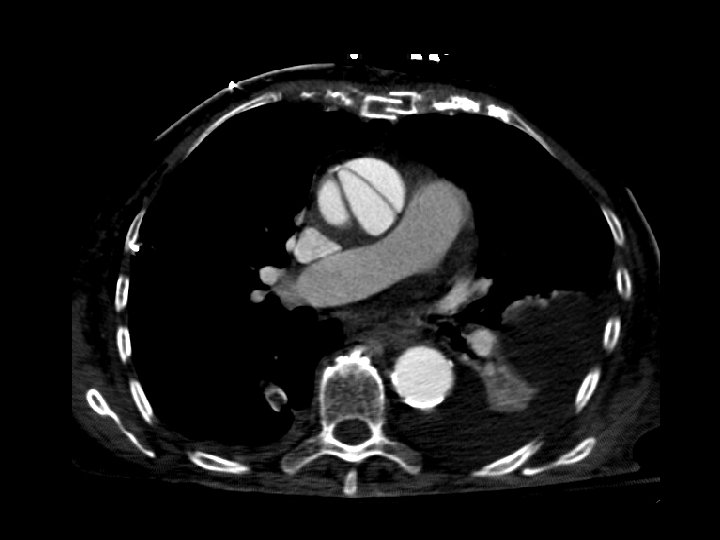

Type A aortic dissection • Findings: – Bilateral pleural effusions – CT is diagnostic • ddx: – NONE! – This is an Aunt Minnie!